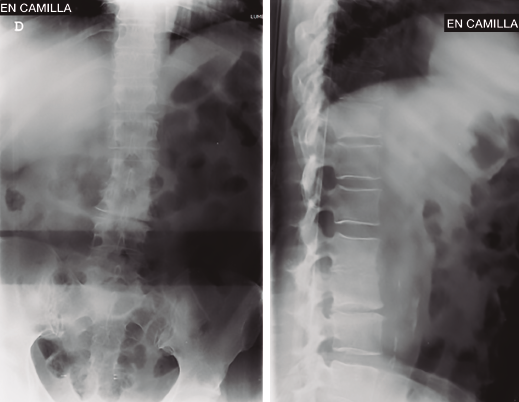

Figura 1. Radiografías iniciales con severa discopatía L2/L3 y discopatía L3/L4.

Se realizó analítica completa: hemograma normal, marcadores proteína C reactiva (PCR) y velocidad de sedimentación globular (VSG) claramente elevados, 80 y 63 respectivamente, Rx y RM (Figuras 1 a 4).

Figura 3. Radiografías al ingreso en nuestra unidad. Seis semanas respecto a las iniciales. Destrucción completa disco L2/L3.